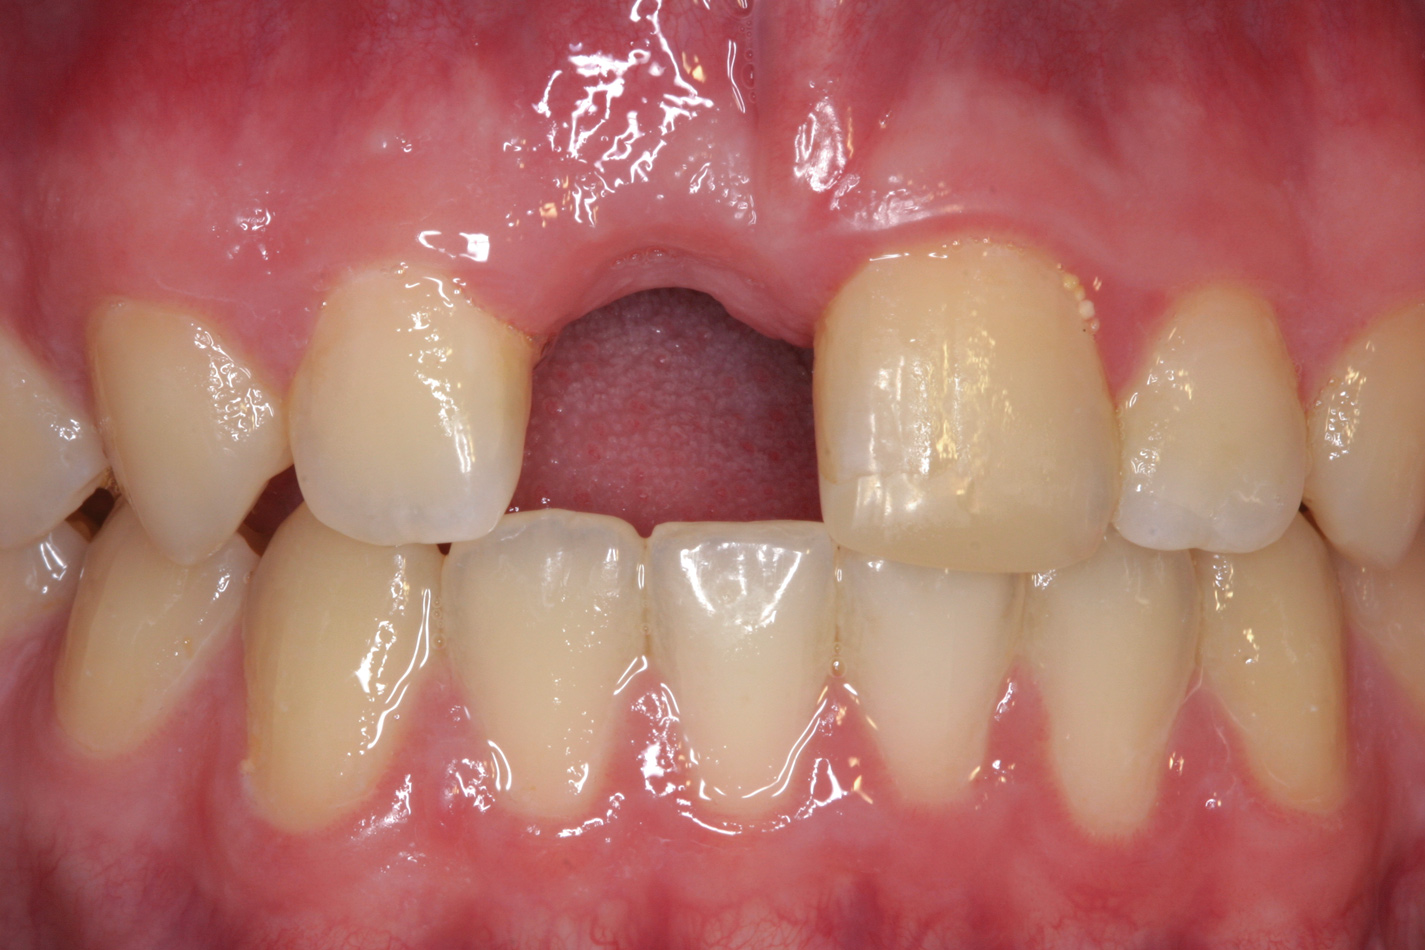

Fig 14. Age 14. Facial view of tooth No. 8 about 2.5 mm in infraocclusion.

Figure 14

The patient returned 4.5 years later, at age 14, for evaluation of his right central incisor. The tooth was now approximately 2.5 mm in infraocclusion (Figure 14). He was asymptomatic, with neither tooth No. 8 nor No. 9 tender to percussion or palpation. No. 9 had normal mobility and the PDL appeared intact radiographically. The radiograph showed No. 8 to have extensive replacement resorption of the root. Gutta-percha was exposed from the mesial CEJ around the apex and down the distal aspect of the root, leaving a sliver of coronal root about 4 mm in length attached to the distal CEJ (Figure 15).

Determining the most appropriate time to decoronate an ankylosed tooth has been discussed in the literature.24-26 Decoronation should take place near the start of adolescent rapid growth when a tooth is approximately one-eighth to one-fourth of the crown height of an adjacent homologous tooth or about 2 mm to 3 mm in infraocclusion. Decoronation at that level of infraocclusion should mitigate the development of a severe alveolar ridge defect.